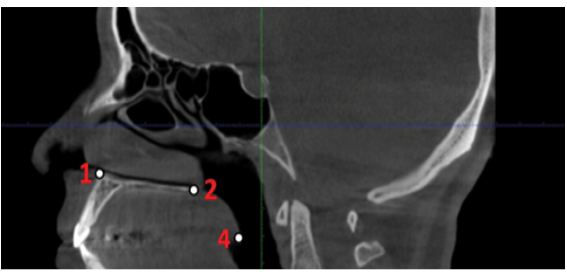

6- Nasal Cavity (NC): The most laterally positioned point on the bony outline of the nasal cavity (Figure-3)

7- Anterior Nasal Spine (ANS): The anteriormost tip of the bony projection arising from the maxilla, located at the inferior border of the anterior nasal opening (Figure-3)

Figure 3. Reference anthropological hard tissue landmarks.